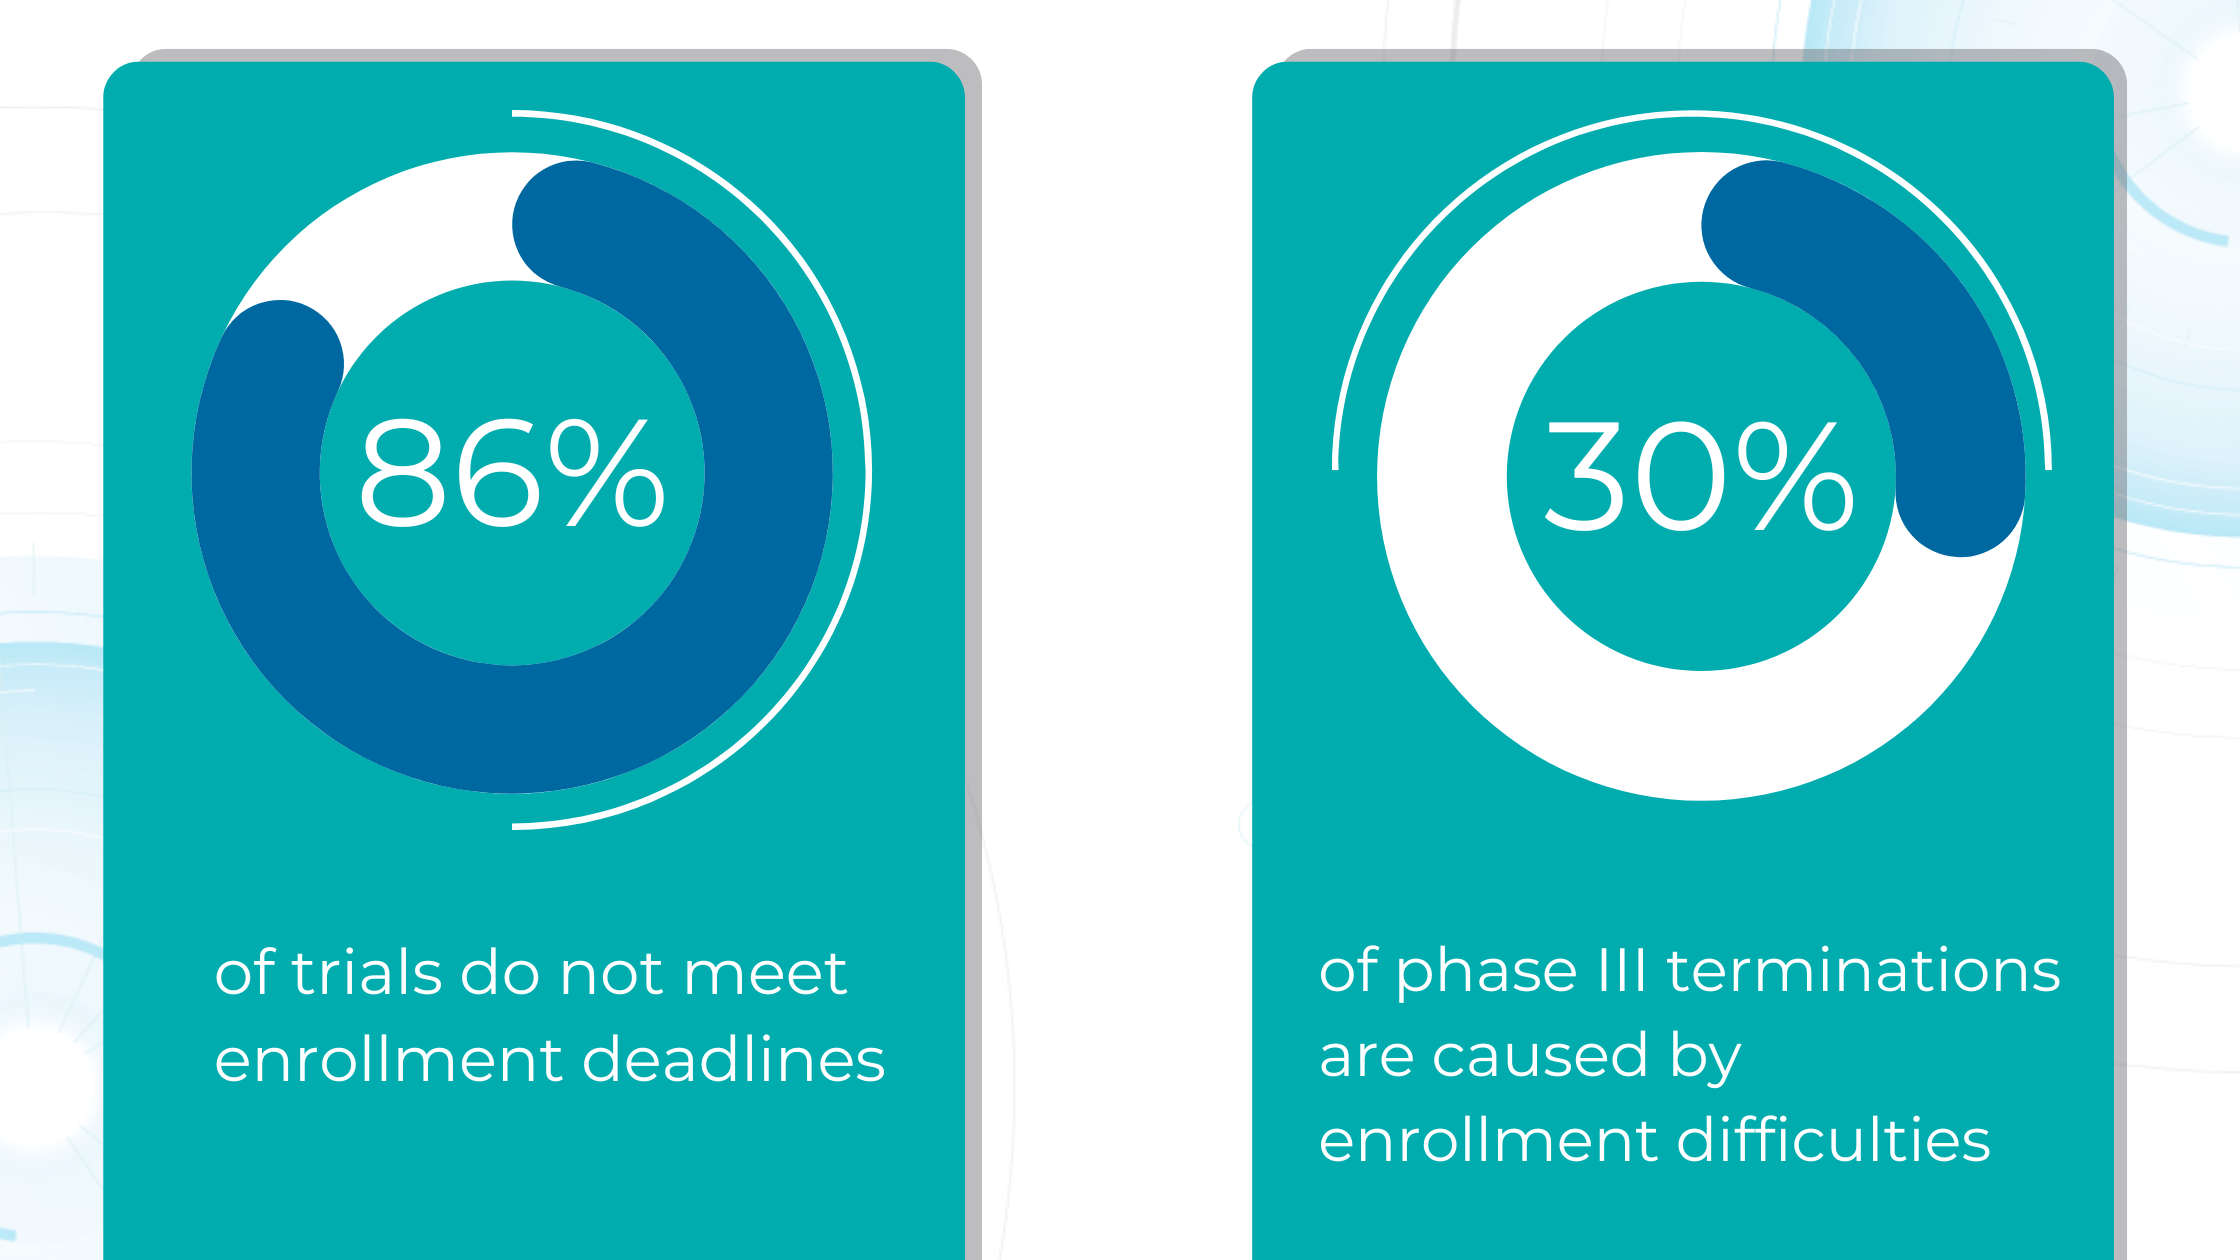

Despite increased research and development spending, fewer novel drugs and biologics are reaching the market today.

Large pharmaceutical companies invest an average of over $5 billion and 12+ years in research and development for each new drug approval.

The high failure rate of drug candidates (only 15% of Phase I drugs reach approval) further exacerbates the issue. This risk often leads pharmaceutical companies to favor lower-risk investments like biosimilars or generic drugs over novel therapies.

Due to their complexity and scale, clinical trials, particularly Phase III trials, consume a significant portion of the budget required to bring a new drug to the market. However, the success rate for compounds entering clinical trials is dismal, with only about one in ten progressing to FDA approval. This high failure rate stems largely from ineffective patient recruitment, as each clinical trial has unique participant requirements, including eligibility criteria, disease stage, and specific sub-phenotypes.